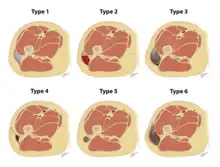

The Mellado-Bencardino classification can be used to describe a Morel-Lavallée lesion based on its MRI.[5] The classification categorizes the lesions into types.[8] The classification has six stages listed as Type I to Type VI.[5] The types do not align with specific treatments or outcomes.[4][8] The stages are based on multiple factors that can be observed on the lesion's MRI.[5] These factors include the following: the shape of the lesion, specific MRI features, and whether a capsule is present.[5][8]